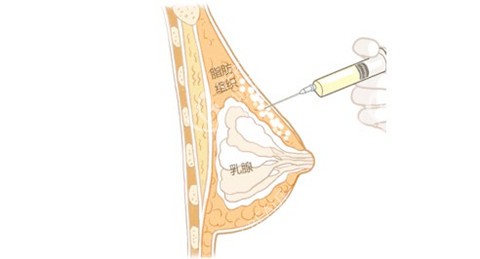

其次,抽取脂肪的部位也很关键。医生通常会选择大腿、腹部等脂肪相对丰富且质量较好的部位。我抽取的是大腿部位的脂肪,这里的脂肪细胞相对饱满,活性较高,移植后存活的可能性也更大。

再者,医生的技术水平起着决定性作用。在提取脂肪时,医生需要采用轻柔、更准一些的操作,避免对脂肪细胞造成过多损伤。如果在提取过程中脂肪细胞受损重的,那么移植后存活的几率就会大大降低。

在填充时,医生要将脂肪均匀地注射到胸部各个层次,让脂肪能够充分接触到周围的组织,获取养分,这样才能提高存活率。